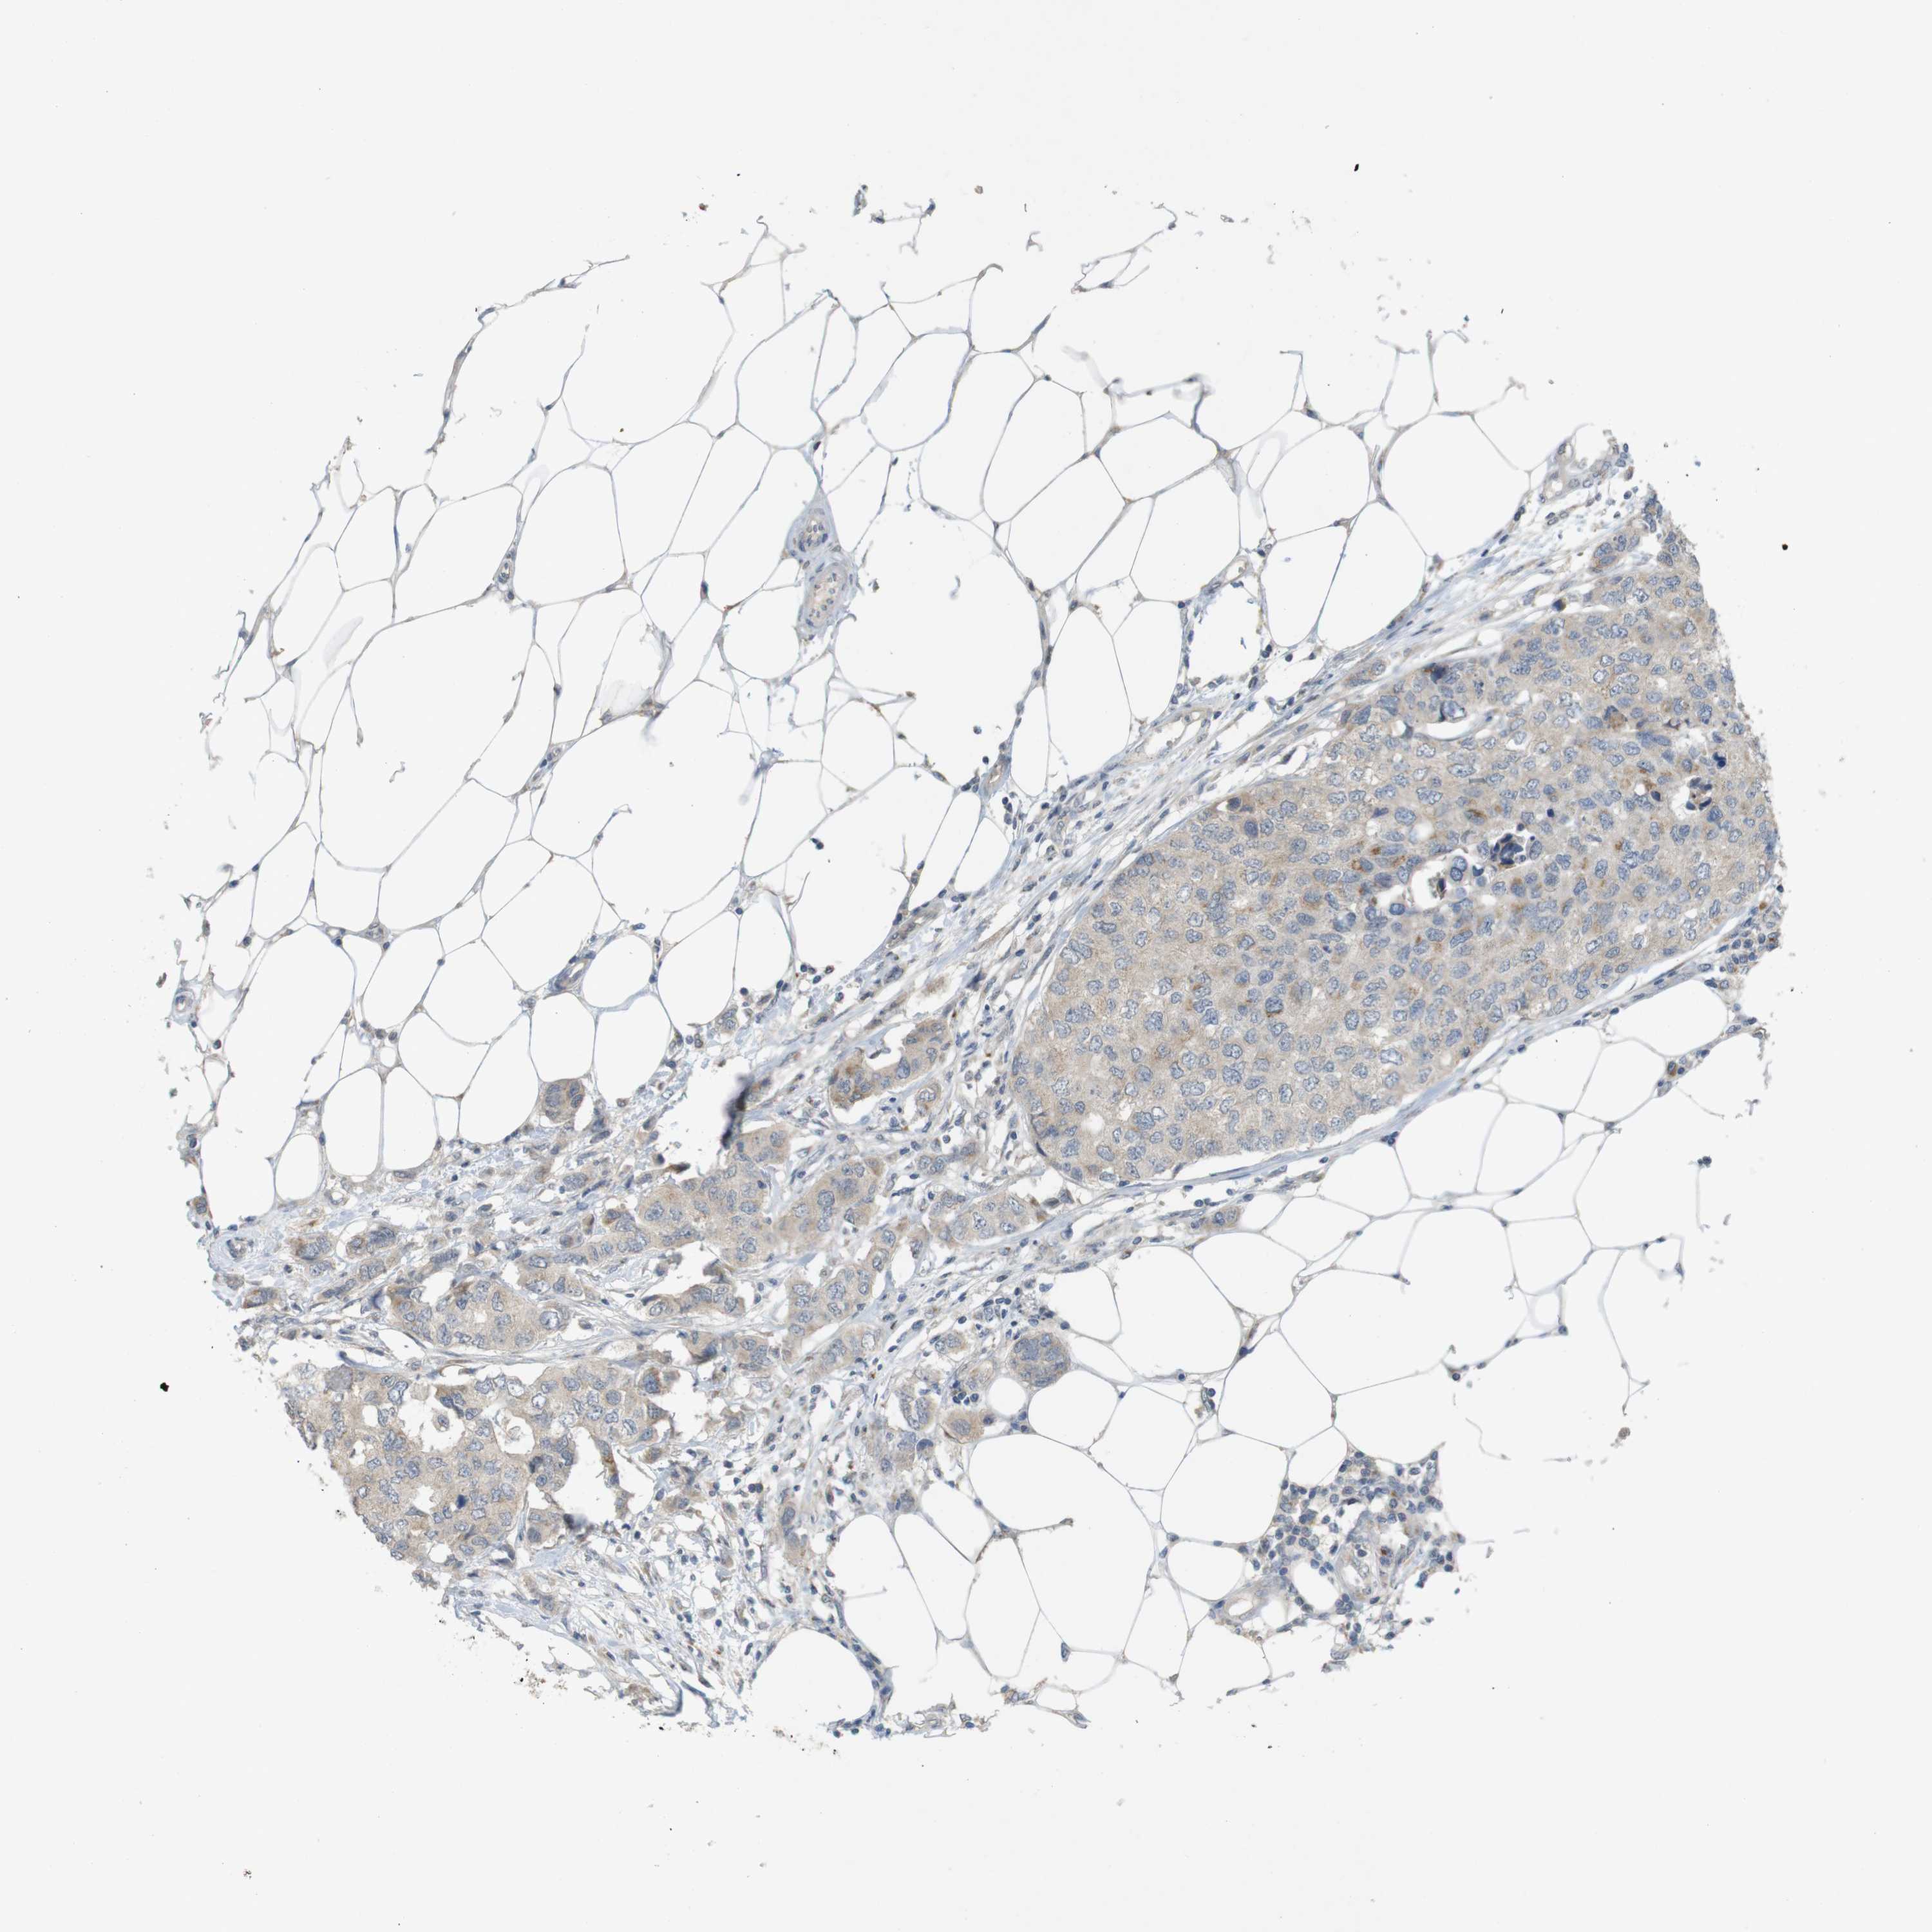

BRCA TCGA BRCA VALIDATION PROTEIN EXPRESSION